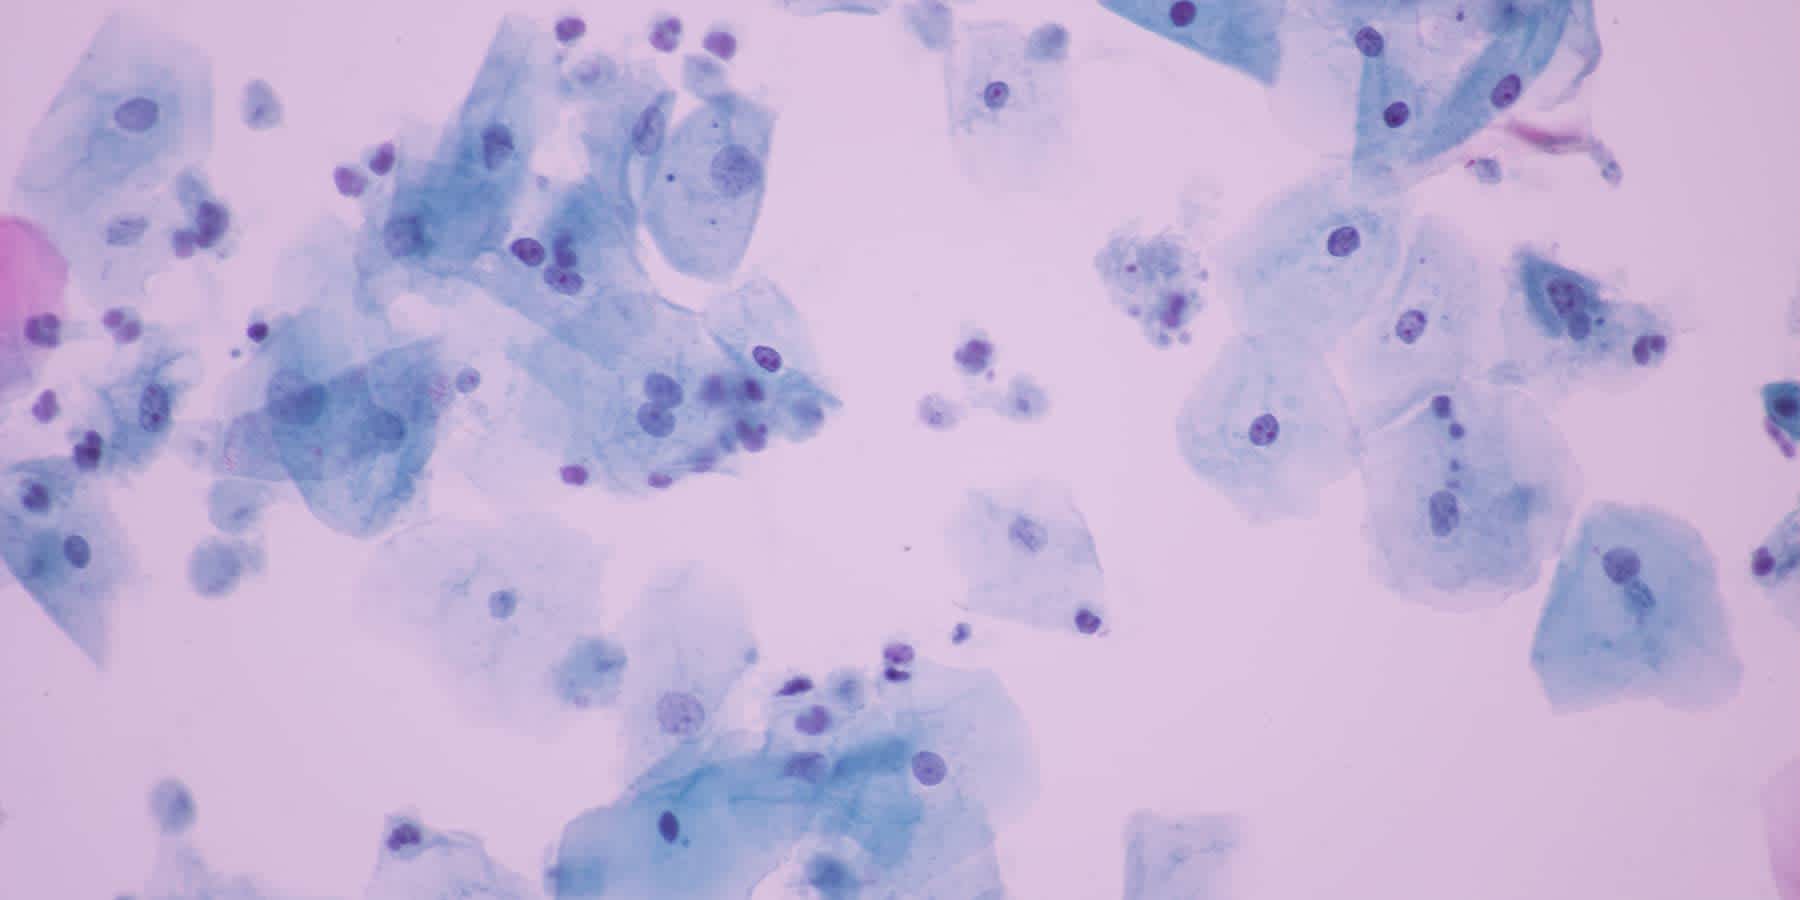

Trichomoniasis is a sexually transmitted disease infection caused by a parasite, specifically a one-celled protozoan. This parasite travels easily through sexual fluids, including pre-cum, semen, and vaginal fluids. It typically infects the vulva, vagina, urethra, and penis, but it usually does not affect the mouth, anus, or other body parts.